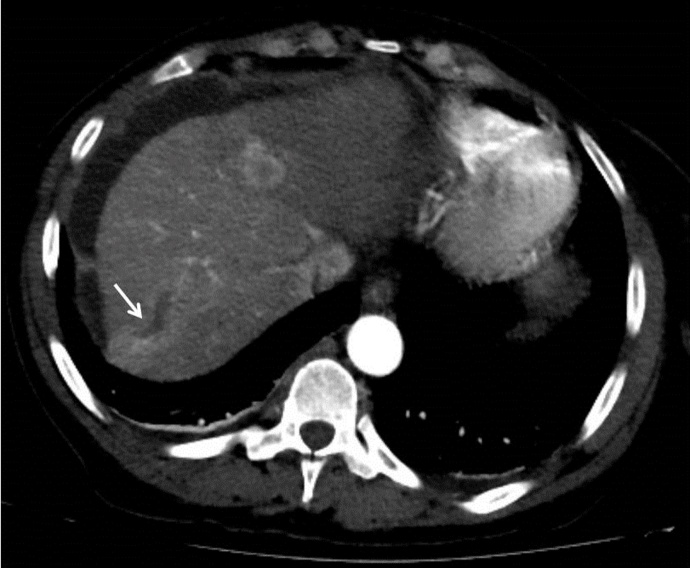

肝细胞癌是美国最常见的肝脏恶性肿瘤之一。预后不良与副肿瘤综合征有关,如高钙血症、高胆固醇血症或低血糖。高钙血症是肝细胞癌的一种副肿瘤综合征,很少有报道。我们报告了一例偶然诊断的肝细胞癌伴恶性体液高钙血症的死亡病例。该患者在最初诊断的40天内表现出暴发性病程,并出现意外的致命结果。我们的病例表明,当肝细胞癌与恶性肿瘤的体液高钙血症相关时,早期明确治疗、密切监测和积极治疗具有重要意义。

Hepatocellular carcinoma is one of the most common liver malignancies in the United States. Poor prognosis is associated with paraneoplastic syndromes such as hypercalcemia, hypercholesterolemia, or hypoglycemia. Hypercalcemia as a paraneoplastic syndrome of hepatocellular carcinoma has been rarely reported. We report a mortality case of incidentally diagnosed hepatocellular carcinoma associated with humoral hypercalcemia of malignancy. The patient demonstrated a fulminant disease course with an unexpected fatal outcome within 40 days of initial diagnosis. Our case can suggest importance of early definitive treatment of hepatocellular carcinoma, extremely close monitoring, and aggressive medical treatment when it is associated with humoral hypercalcemia of malignancy.